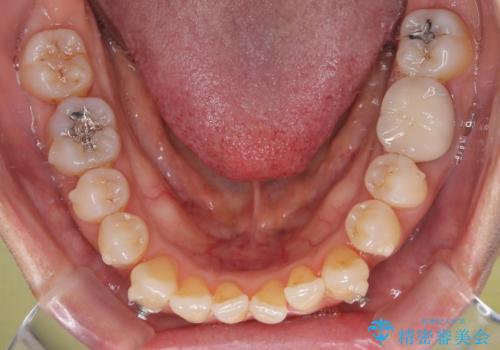

受け口と八重歯を改善 インビザライン矯正治療

- インビザライン

- 2年5ヶ月

受け口傾向の骨格であり、前歯はクロスバイトまたは切端咬合となっており、下顎を中心に歯列全体の後方移動を行い、IPR(歯と歯の間を削る)によってデコボコが解消するように設計し、インビザラインにより治療を行うこととしました。

受け口傾向のインビザライン矯正は比較的治療を行いやすいため、きれいに仕上げることができました。舌の突出癖が顕著であったため、改善のためのトレーニングをしっかりと行っていただきました。